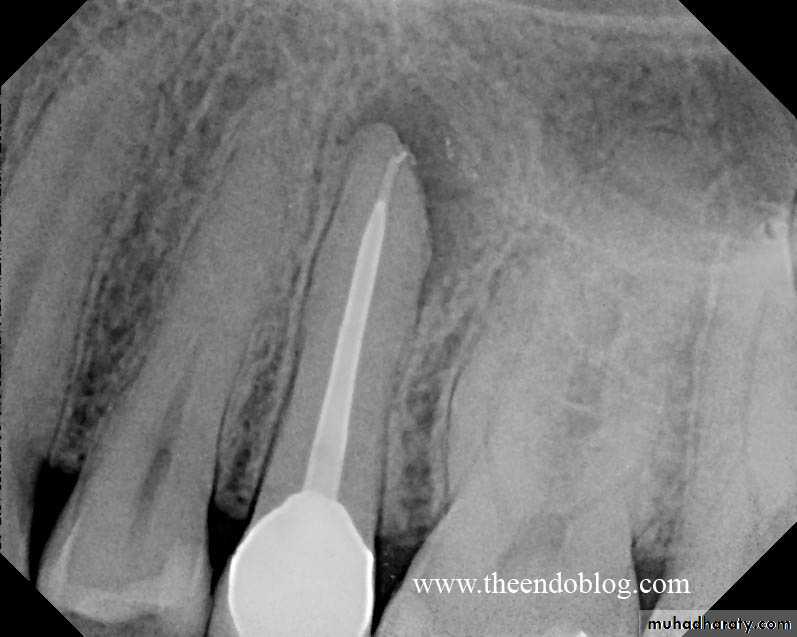

Radiographic features:

Initially, No radiographic change.

With progression, slight widening of PDL, lamina dura may become less defined.Histopathological features: